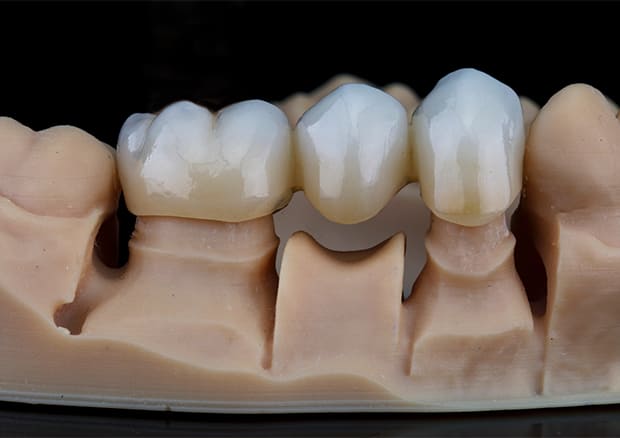

CASE.01

左下のフルジルコニアブリッジで

修復した症例

- 主訴

- 歯がないところを治したい

- 治療法

- 左下にフルジルコニアブリッジで修復

- 治療期間

- 1ヶ月半

- 費用

- ¥240,000(税込)

【リスク・副作用】

過度の咬合や衝撃で割れることがあります。治療直後は歯や歯茎に一時的な違和感や痛みが出ることがあります。